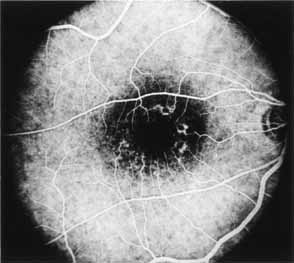

Fluorescein angiography demonstrates increased transmission of choroidal fluorescence in the macula during early phases of the study, without late leakage of dye or fluorescein staining. In addition, an annular pattern of hyperfluorescence is often seen in the macula, highlighting the bull's-eye pattern seen on fundus examination (Fig. 4). Visual field defects include central scotoma, peripheral field loss, and ring scotoma.